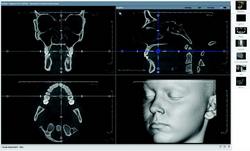

3-D software can shade images to differentiate varying densities of facial structures. Grayscale shading provides the ability to view the relationships of common internal anatomy. Traditional CT imaging renders an 8-bit grayscale (256 shades) or 12-bit grayscale (4,096 shades). Present-day scanners render images in 14-bit grayscale, providing 16,384 shades. Color coding the image by density further distinguishes anatomical structures, enabling the clinician to view pertinent anatomy while planning implant cases, such as nerves and nasal cavities, and mandibular and maxillary dimensions. Segmentation literally cuts the volume rendering, conceding top views, side views, and CT slices that produce unlimited axial, coronal and sagittal views. CBCT slices are as thin as 0.1 mm, compared to 1 mm for a conventional fan CT scan.

CBCT devices may be used for traditional forms of radiography, in addition to advanced 3-D volumetric renderings. Conventional cephalometric measurements may be obtained through 3-D volumetric images by rendering the image as a 2-D projection resembling a radiograph or a panoramic image. It is also possible to digitize cephalometric points in 3-D, resulting in the introduction of multiple analyses.